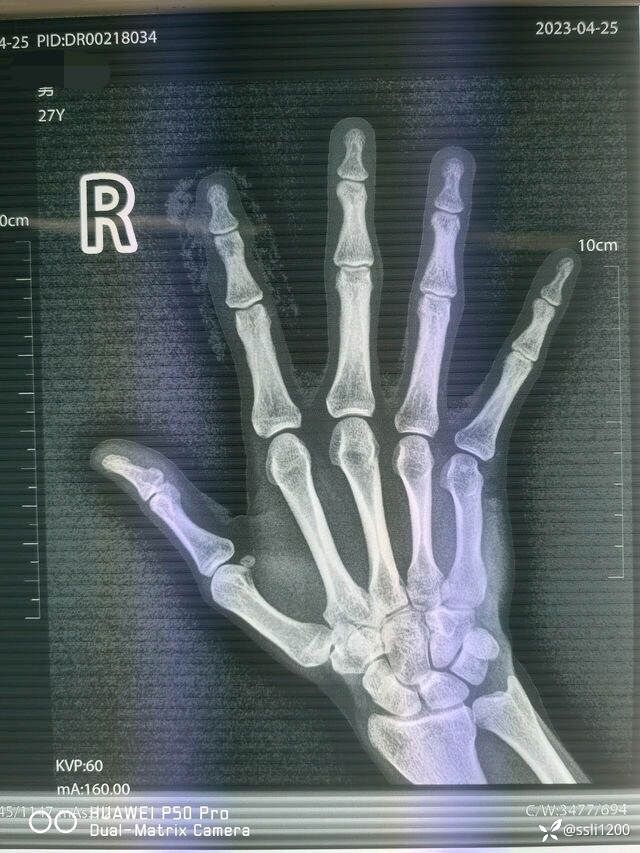

辅助检查:2023-04-25 本院DR检查提示:右示指骨质未见明显异常。

术前DR